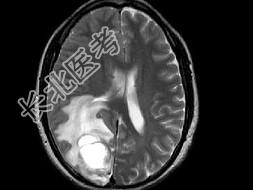

- 单项选择题女,46岁, 头痛、头昏半月入院,根据所提供图像, 最可能的诊断是 ( )

A、转移性乳头状腺癌

B、胶质瘤

C、脑脓肿

D、胶质母细胞瘤

E、毛细胞型星形细胞瘤